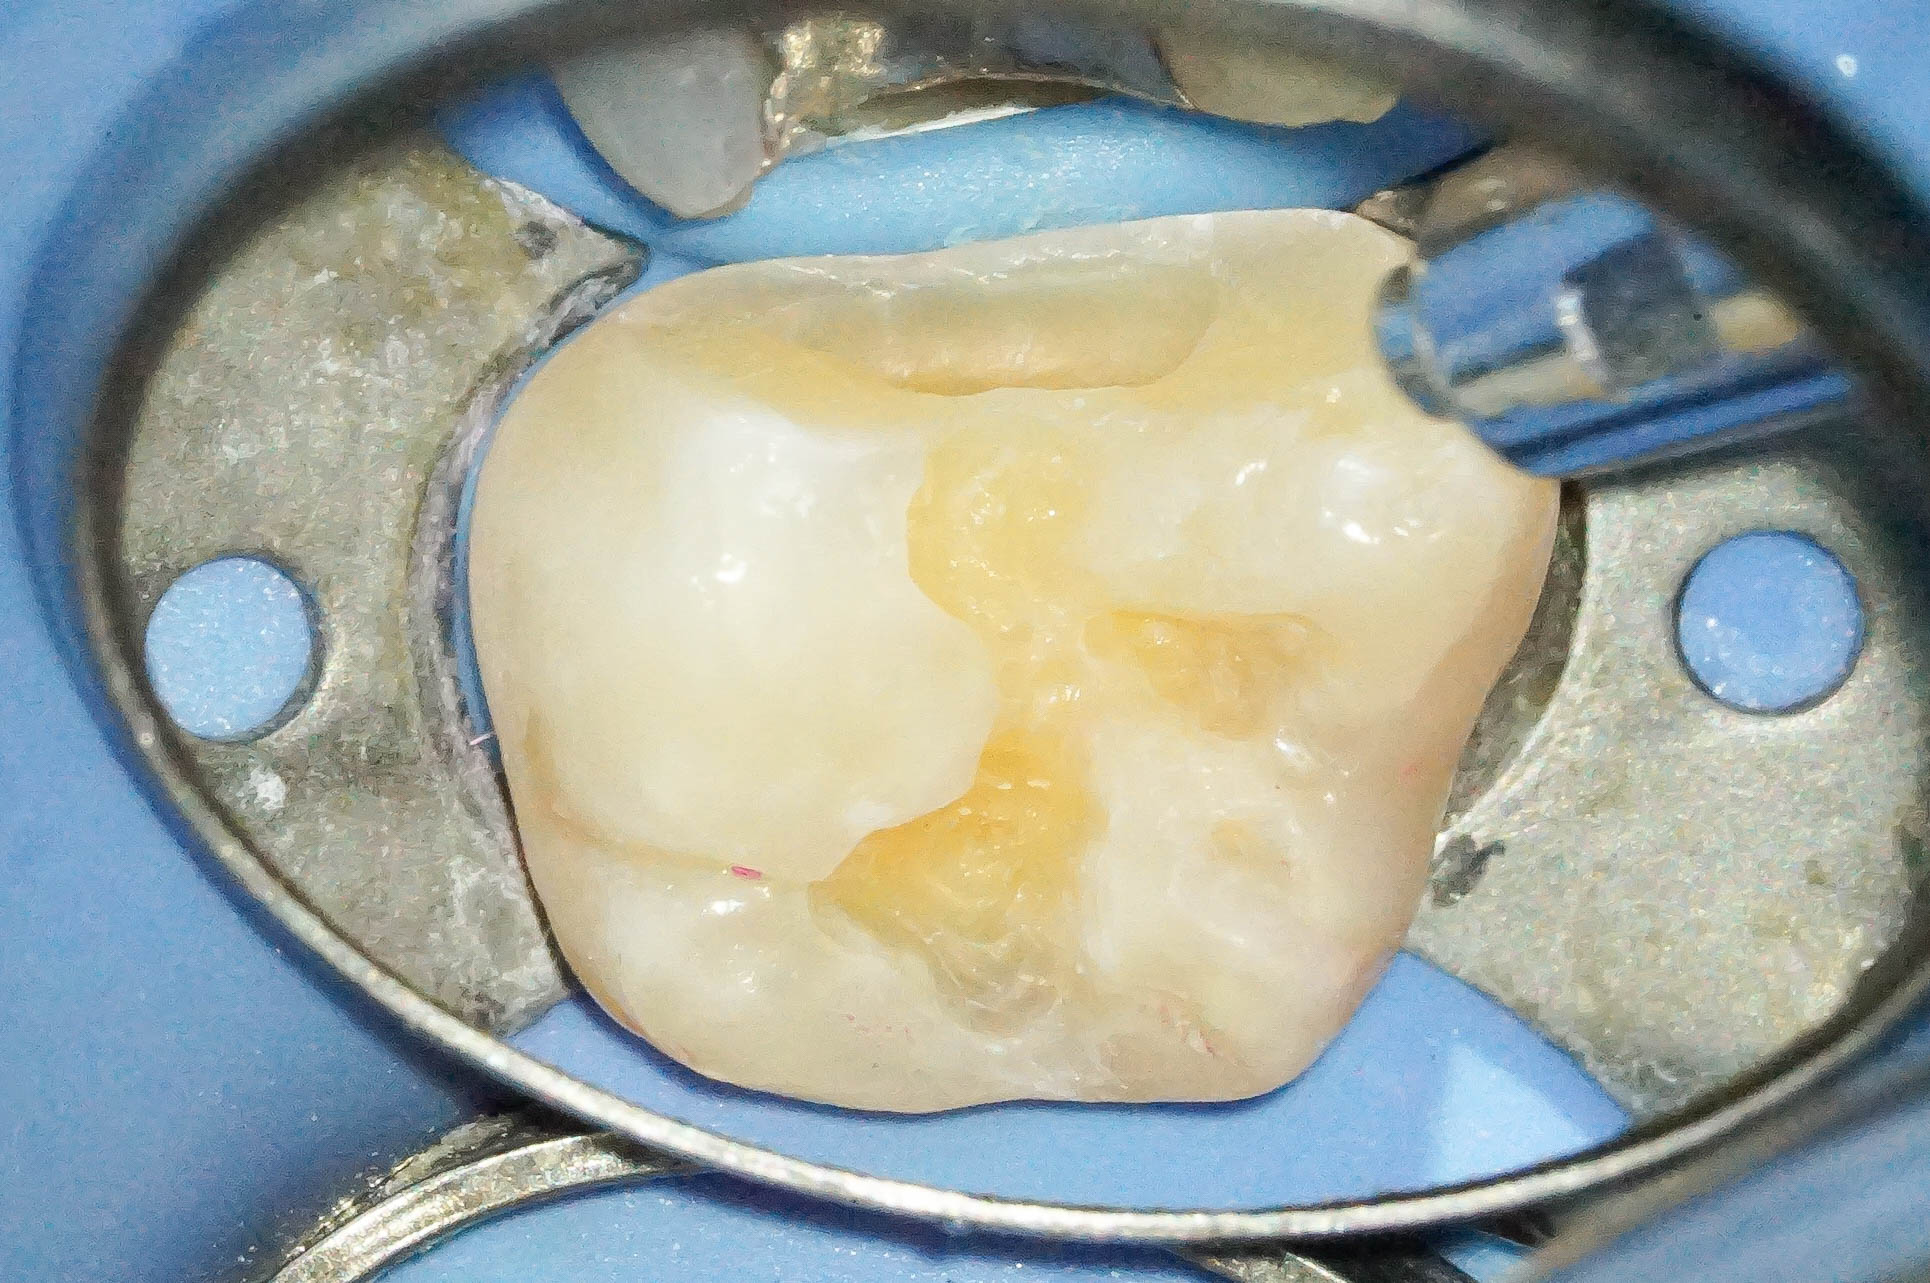

歯肉縁下ダイレクトボンディングを行った症例治療方法05

古いコンポジットレジンを除去したところ、やはり内部でウ蝕が広がっていました。

確実な視野の確保、そして清潔な領域を守りつつ作業ができるので、ラバーダムの効果は絶大です。

歯肉縁下ダイレクトボンディングを行った症例治療方法06

ウ蝕検知液を使用して徹底的に軟化象牙質を除去していきます。